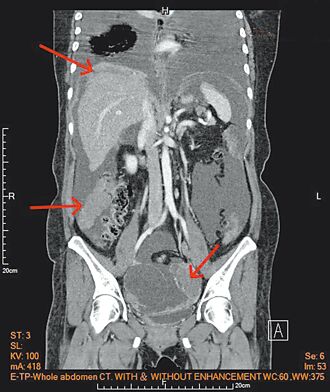

人體若長期發燒,千萬別輕忽!醫師江坤俊日前分享,一名37歲男子半年來反覆發燒,卻無其他症狀,直到體重下降,才趕緊就醫檢查。但從抽血、驗尿,再掃電腦斷層,幾乎「從頭到腳」檢查一遍,仍找不出原因,最後是一粒藥證實醫師推測,男子罹患了罕見的腹膜癌。

發燒常是身體出狀況的警訊。一名37歲男子,近半年來,三不五時就會發燒,醫師懷疑男子罹癌,但做了抽血、照了電腦斷層,都查不出異樣,後來請男子試著吃抗腫瘤熱的藥,男子一周都沒發燒,此時醫師更加篤定男子罹癌的臆測,再經正子攝影與開刀採檢,證實男子罹患的是末期腹膜癌。